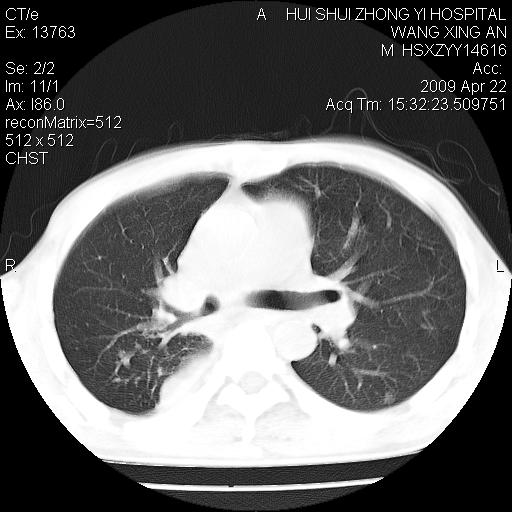

标题: CT19534:患者男、46岁咳嗽、胸痛半月。 [打印本页]

标题: CT19534:患者男、46岁咳嗽、胸痛半月。

1、右下肺中央型肺癌并右肺转移,右肺下叶不张。(肿块围绕右肺下叶支气管生长,致管腔闭塞右肺下叶不张;右肺有结节影)。

2、右侧胸腔积液。

3、右中上肺陈旧性肺结核(右肺见纤维化病灶及点状钙化)。